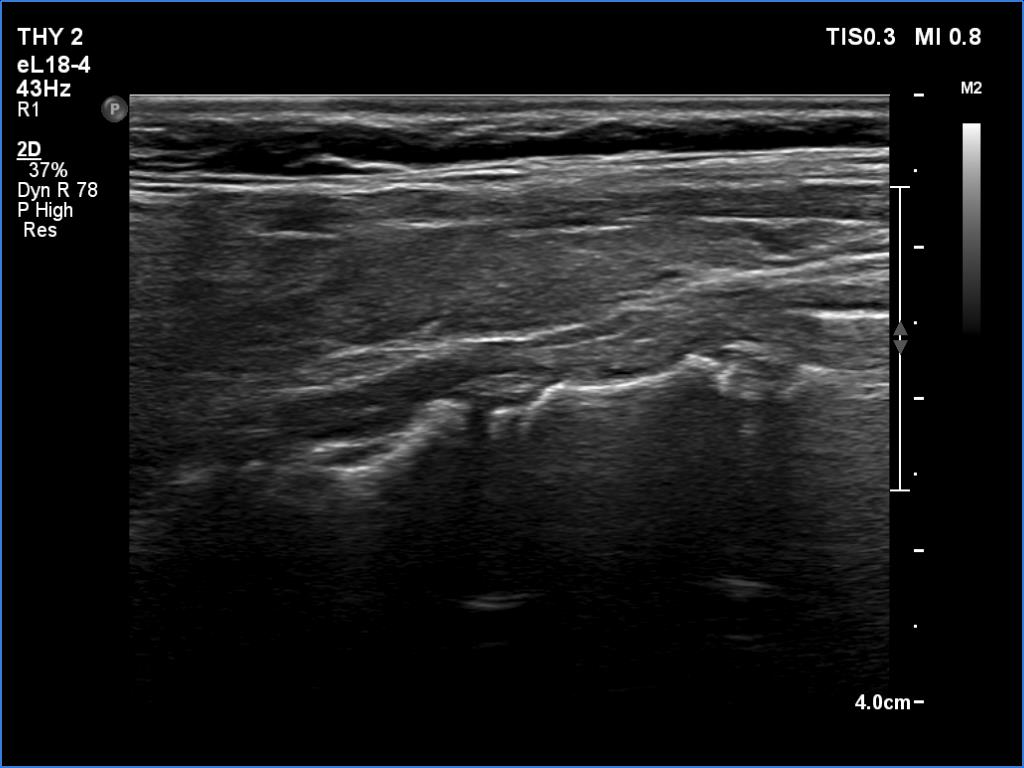

Lymphocytic thyroiditis - case 1441

Right lobe

Left lobe

Focal form of lymphocytic thyroiditis is presented. The thyroid has numerous discrete, hypoechoic lesions which correspond to more active foci of thyroiditis. The interpretation of the relatively large ventral hypoechoic area in the left lobe (right upper image can cause problem), however, longitudinal scan decides the issue: this field cannot be a pathological nodule.